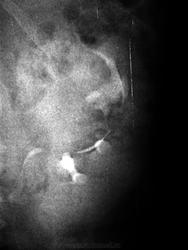

Поступила женщина 60 лет с клиникой нечеткой почечной колики после "перетруждения" на огороде, с жалобами на бурую мочу (которая к утру стала прозрачной и ничего, кроме микрогематурии не зафиксировалось). На эксреторке - такая картинка (продолжение темы насчет фантазии в рентгенологии).

А вот чем - тут действительно, поле для фантазии есть (еще и с учетом эпизода макрогематурии). Тумор? - УЗИ.

Доброкачественная опухоль? Чашечки раздвинуты

Они то раздвинуты, но местами как бы "погрызены"))))

Раз по внутривенке не можем уверенно дифференцировать характер объёма, прямые признаки злокачественного процесса не очень убедительны - дальнейшее гадание (на тему гипернефрома, аденокарцинома, киста и т.п) не имеет смысла без уточняющих методик диагностики (личное мнение).

Рак почки длительное время растёт без клиники. Смещение верхней и средней групп чашек, их деформация, обрывов и дефектов не вижу. Думаю большая киста. Томограммами уро не занимался

Возможно такой вариант. Парапельвикальная киста почки, обычно имеет округлую или овальную форму, жидкость в ней может быть как прозрачной, так и иметь желтоватый оттенок.

2. Экскреторная урография – на изображении заметны деформированные лоханки, смещение мочеточника, наличие округлой тени примыкающей к почке.

УЗИ было до внутривенки. Жидкостное круглое образование с ровными внутренними стенками.

По УЗИ: картина кисты. Микрогематурия, возможно была обусловлена конкрементом. И все же, для уточнения - КТ.